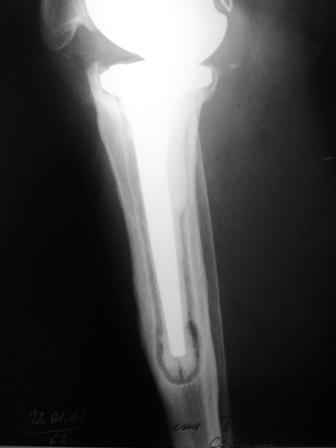

Уважаемые коллеги!Хотелось бы услышать Ваше мнение о возможности и способе помощи больной. 1939 г.р. В 1995г. эндопротезирование правого коленного сустава протезом Феникс, в 1999г. в г. Томске - ревизия - ротационный хинч W.Link. C 2005г. прогрессирует варусная деформация за счетнестабильности тибиального компонента. Попытка ортезирования - без эффекта. Попытка направить в ФСМУ без эффекта, да и больная не хочет никуда ехать.С уважением, Leonid

Технически можно надеть гвоздь на ножку протеза

Понятно что для решения на операцию артродеза необходимы веские причины. Но я не уверен что здесь асептическое расшатывание. Судя по снимкам, бедренный компонент стоит не плохо, и есть рассасывание костной ткани вокруг всего протеза в голени. Что-то мне подсказывает об инфекционном процессе, возможно вялотекущем. В наших условиях я сделал бы обследование включающее анализы крови с СОЭ, СРБ. Сделал бы пункцию коленного сустава или даже биопсию мягких тканей для посева и микроскопии.

Изотопное сканирование с технецием и с мечеными лейкоцитами. PET-CT. И после этого легче принять решение. Если есть инфекция, то необходимо выполнить лечение этапное в котором первый этап удаление протеза и установка цементного спейсера с лечением АБ 6-8 недель. Если победите инфекцию, что видно по показателям СРБ и СОЭ, то через 3-6 месяцев можно вернуть протез.